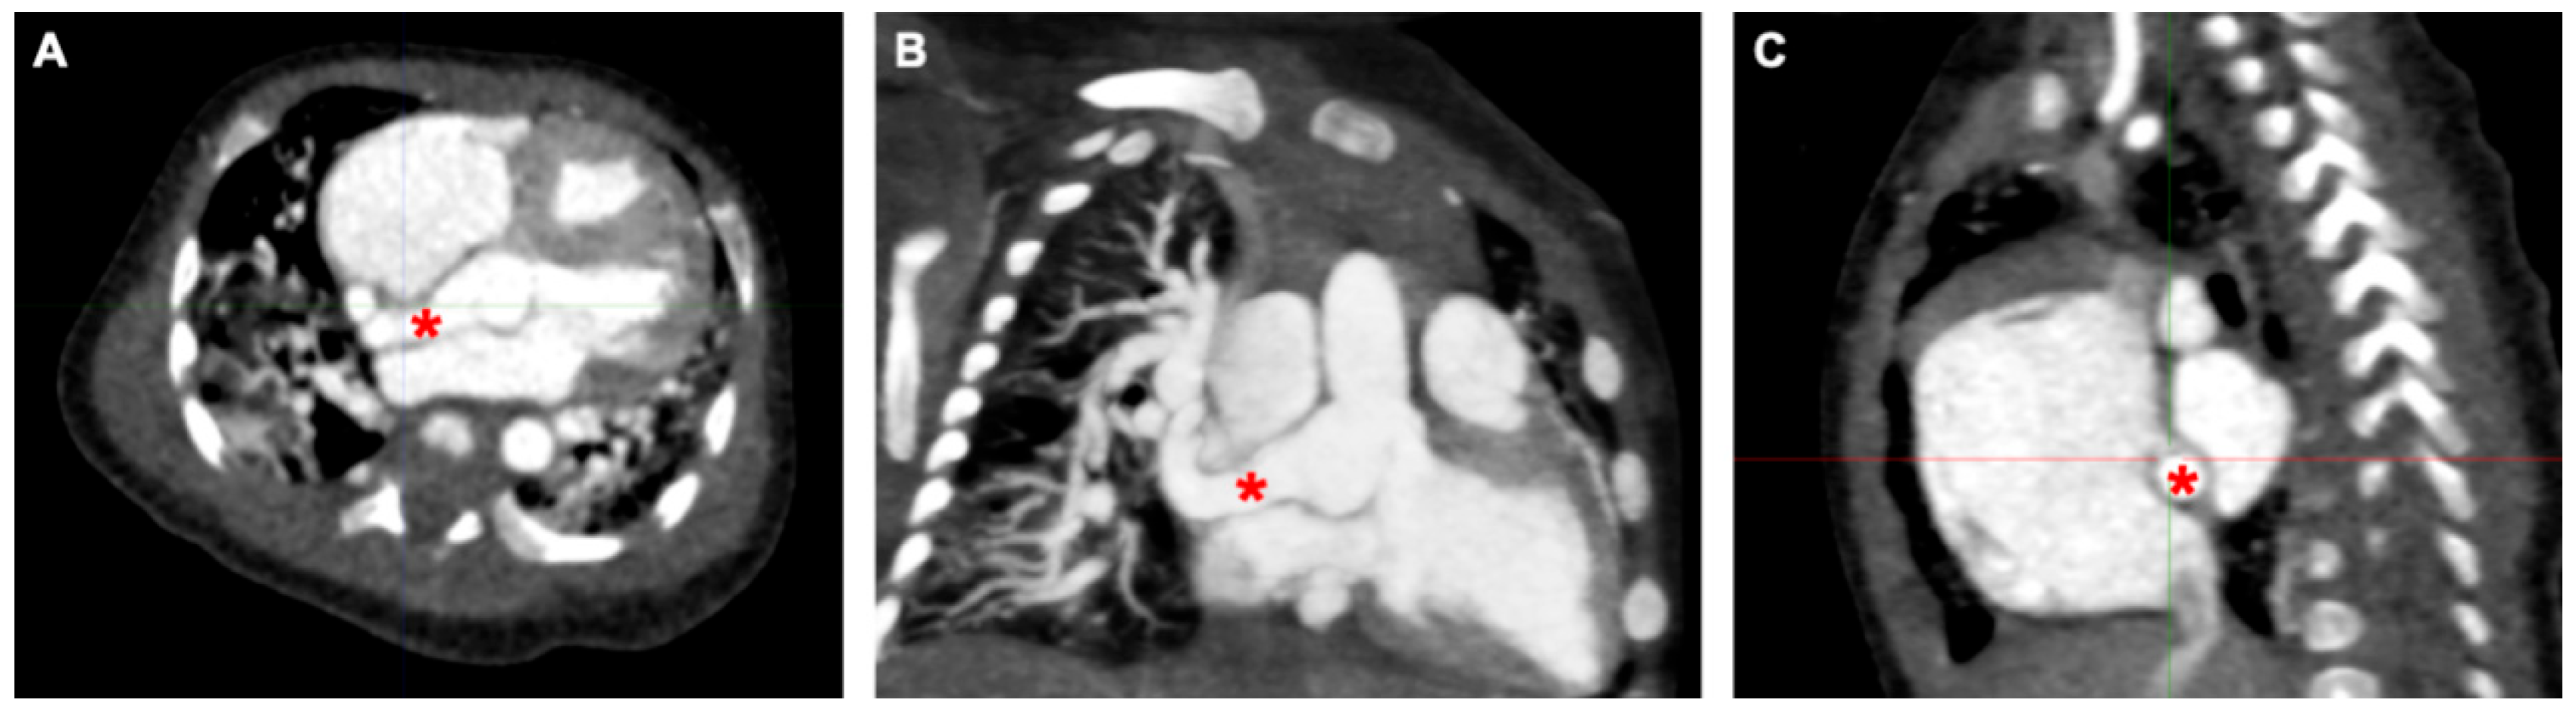

An echocardiogram revealed a dilated right atrium and ventricle with a normal left ventricular size and function. The aortic valve was tricuspid with mild aortic regurgitation. The noncoronary sinus of Valsalva (NCS) was dilated with a continuous turbulent flow between the NCS and the right atrium, which was approximately 8 mm in diameter. An atrial septal defect (ASD) (10 mm) was detected. To confirm the diagnosis of aorta–right atrial tunnel, a multidetector computed tomography angiography (CTA) was performed. CTA revealed that the left and right coronary arteries and branches were normal. The NCS was enlarged, from which a tortuous tunnel originated and terminated at the right atrial–superior vena cava junction (Fig. 1 and Fig. 2).

Figure 2: Three-dimensional reconstruction of the cardiac structure based on CT images using the Mimics software, viewed from the posterior aspect. The yellow channel represents ARAT, arising from the dilated noncoronary sinus, coursing posterior to the right atrium. CT, computed tomography; ARAT, aorta–right atrial tunnel.